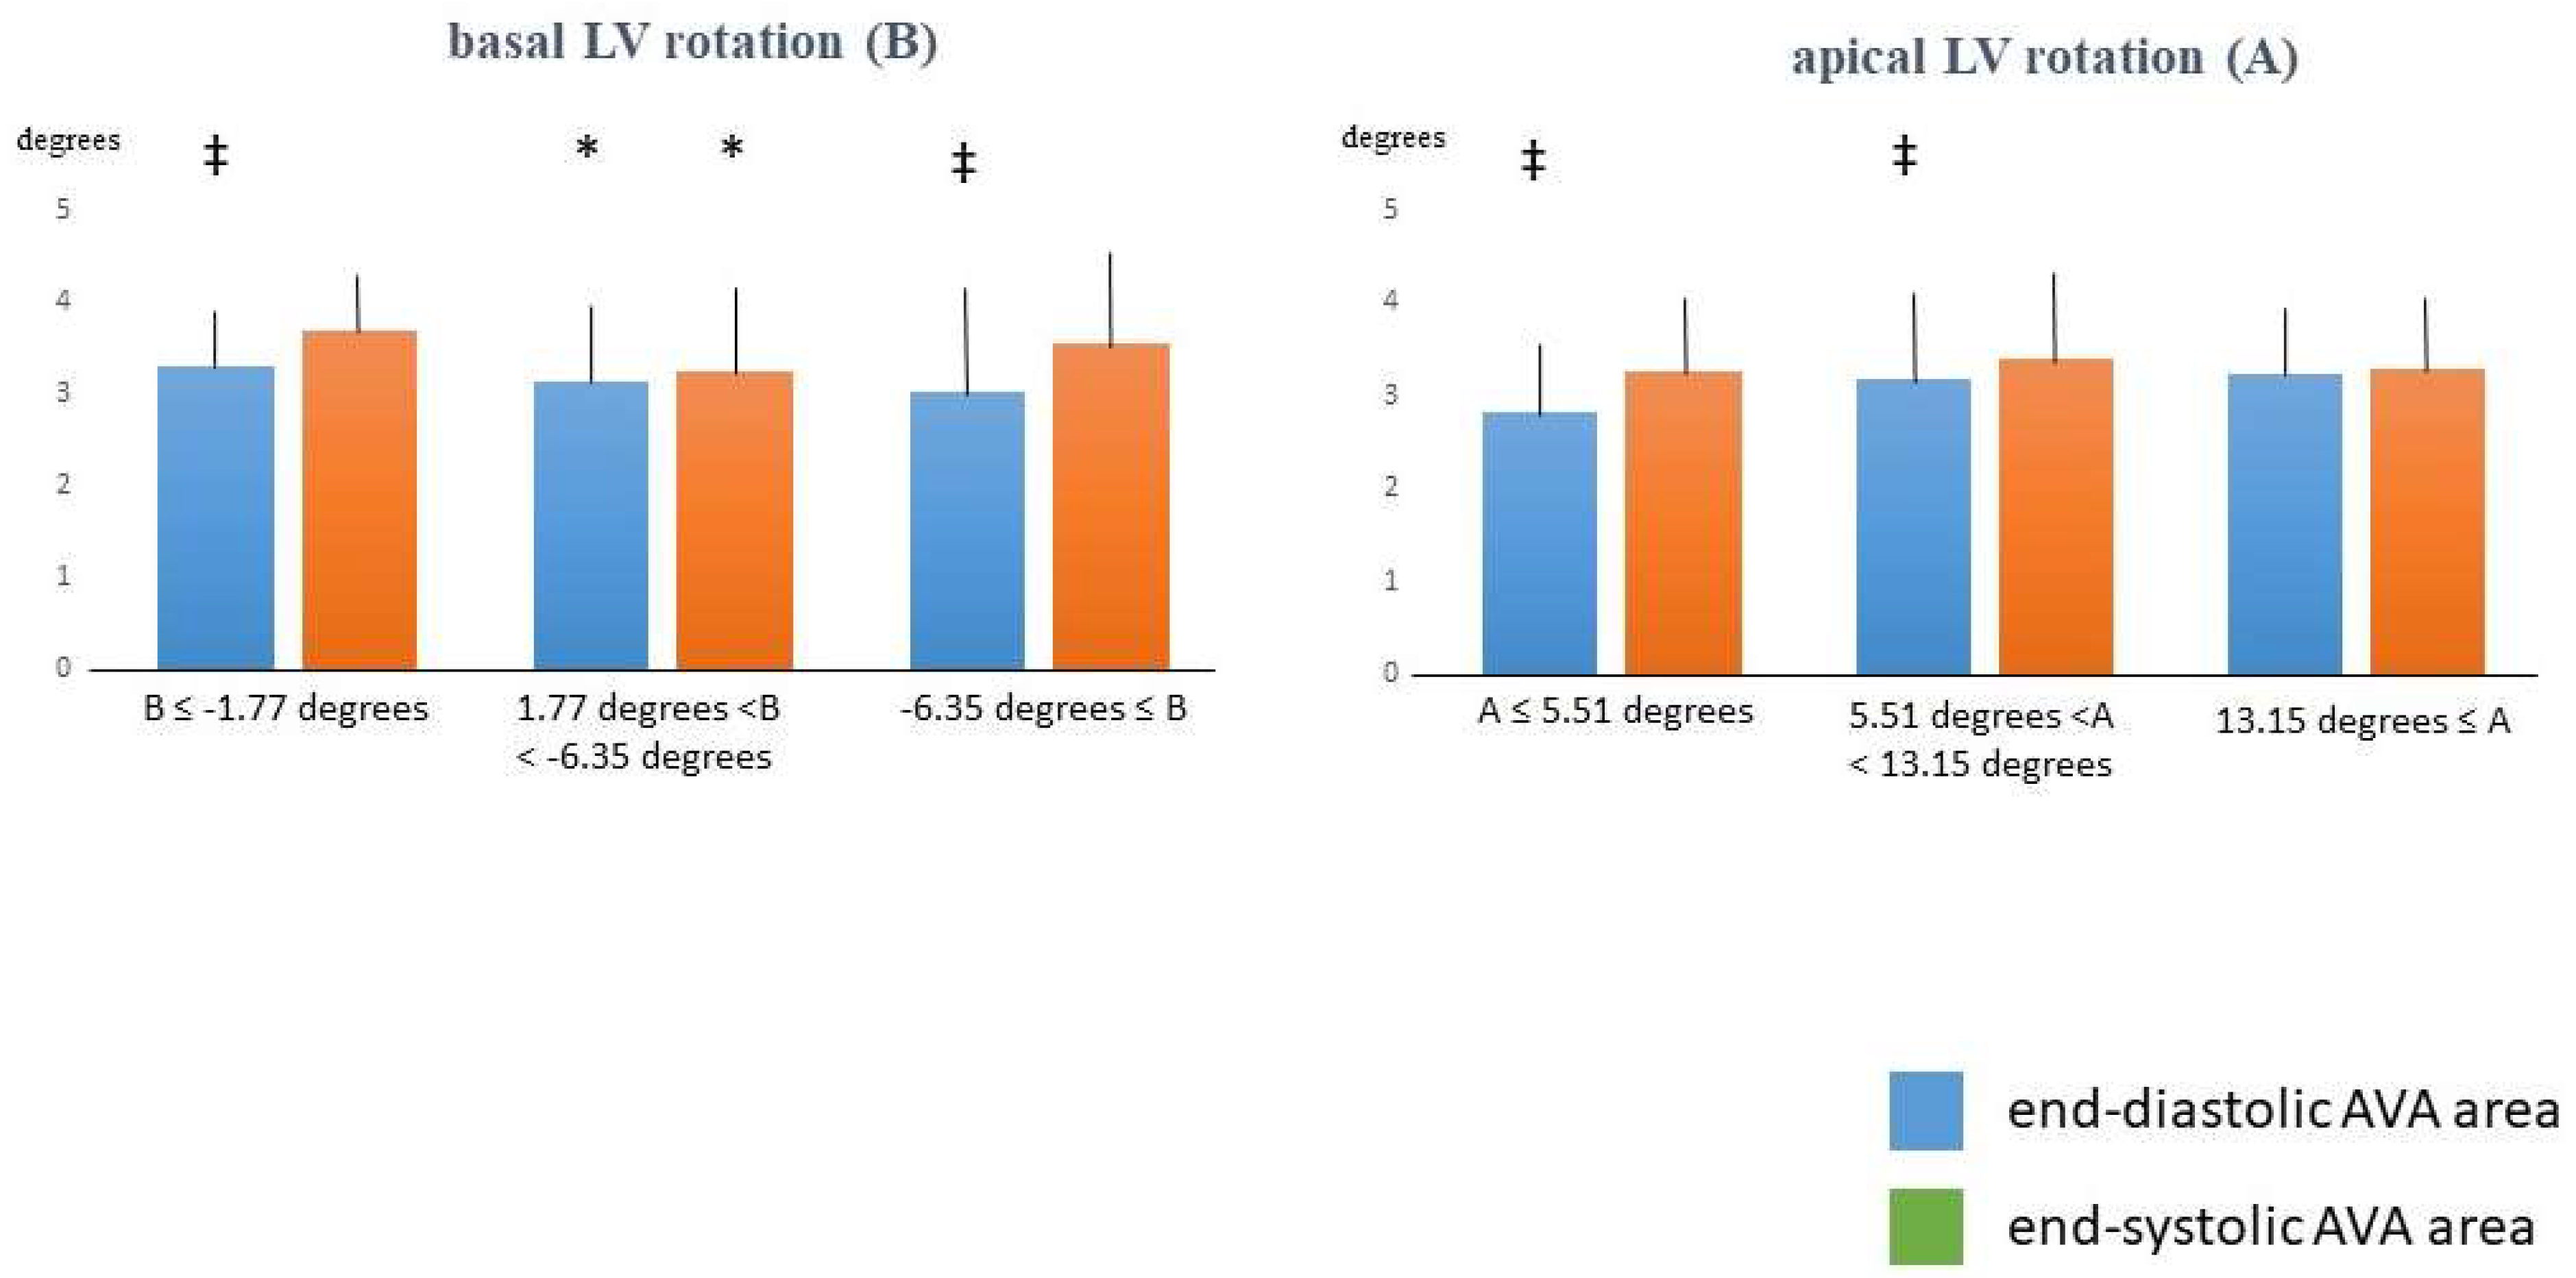

3. Results

| Basal LV Rotation ≤ −1.77 Degrees (n = 14) | −1.77 Degrees < Basal LV Rotation < −6.35 Degrees (n = 77) | Basal LV Rotation ≥ −6.35 Degrees (n = 20) | Apical LV Rotation ≤ 5.51 Degrees (n = 16) | 5.51 Degrees < Apical LV Rotation < 13.15 Degrees (n = 77) | Apical LV Rotation ≥ 13.15 Degrees (n = 18) | |

| ED-AVA-Dmax (mm) | 2.08 ± 0.22 | 2.02 ± 0.32 | 1.98 ± 0.34 ‡ | 1.96 ± 0.37 | 2.02 ± 0.31 ‡ | 2.09 ± 0.25 |

| ED-AVA-Dmin (mm) | 1.95 ± 0.16 | 1.81 ± 0.30 * | 1.78 ± 0.32 ‡ | 1.71 ± 0.31 | 1.84 ± 0.30 ‡ | 1.83 ± 0.26 |

| ED-AVA-A (mm) | 3.30 ± 0.53 ‡ | 3.14 ± 0.84 * | 3.02 ± 1.05 ‡ | 2.83 ± 0.78 ‡ | 3.18 ± 0.89 ‡ | 3.24 ± 0.69 |

| ED-AVA-P (mm) | 6.49 ± 0.52 ‡ | 6.31 ± 0.87 * | 6.16 ± 1.03 ‡ | 6.00 ± 0.90 ‡ | 6.33 ± 0.90 ‡ | 6.44 ± 0.67 |